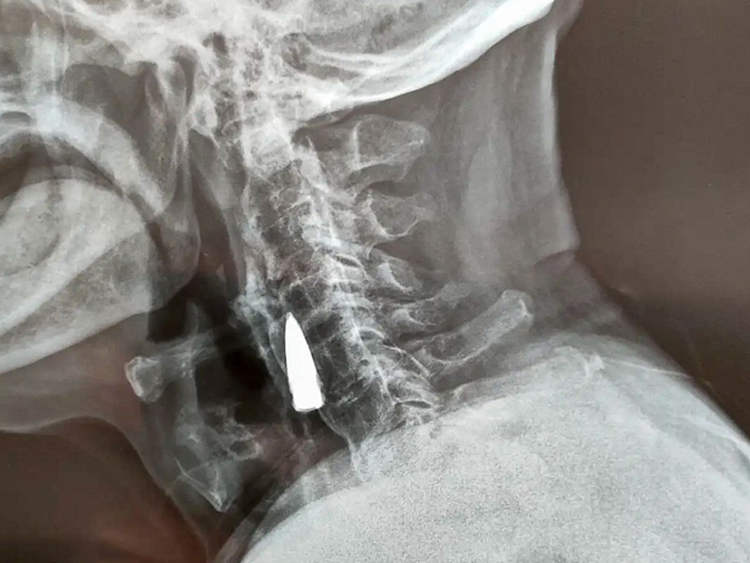

Αφού άκουσαν για την πτώση του, οι γιατροί του συνέστησαν μια ακτινογραφία, για να βεβαιωθούν ότι δεν είχε υποστεί σοβαρή βλάβη στον αυχένα του. Μόνο που αντί για κάταγμα, η ακτινογραφία αποκάλυψε ένα ξένο αντικείμενο στο λαιμό του άνδρα, το οποίο αργότερα θα αναγνωριζόταν ως μια παλιά σφαίρα.

Ο ίδιος ο Ζάο εκτιμά ότι η σφαίρα βρισκόταν στο λαιμό του από το 1944, όταν χτυπήθηκε από σφαίρα ενώ διέσχιζε ένα ποτάμι. Η σφαίρα φέρεται να μπήκε μέσα από την αριστερή πλευρά της μύτης, διαπέρασε την άνω γνάθο του και του έβγαλε ένα από τα δόντια του πριν σφηνωθεί στον λαιμό του. Ωστόσο, αυτό είναι μόνο το προαίσθημά του.

Αφού εξέτασαν τις ακτινογραφίες, οι γιατροί είπαν στον Zhao He και την οικογένειά του ότι η σφαίρα ήταν κοντά σε κάποια σημαντικά αιμοφόρα αγγεία και ότι, εφόσον δεν του είχε προκαλέσει κανένα πρόβλημα, ήταν καλύτερο να την αφήσουν μέσα. Ο βετεράνος πολέμου συμφώνησε.